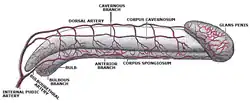

O pénis humano é formado por três colunas de tecido: dois corpos cavernosos situam-se lado a lado no lado dorsal e um corpo esponjoso entre eles no lado ventral.[11]

O pénis humano difere da maioria dos outros mamíferos, pois não possui o báculo (ou osso erétil) e, em vez disso, depende inteiramente do ingurgitamento de sangue para atingir seu estado ereto. Um ligamento distal apoia a glande do pénis e desempenha um papel integral no fibroesqueleto peniano, e a estrutura é chamada de "os analog", um termo cunhado por Geng Long Hsu na Encyclopedia of Reproduction.[15] É um remanescente do báculo que evoluiu provavelmente devido à mudança na prática de acasalamento.[16]

O pénis humano é maior do que a média no reino animal em proporção à massa corporal. O pénis humano alterna de um algodão macio para uma rigidez óssea resultante do fluxo arterial peniano variando entre 2-3 a 60-80 mL /min implica o meio mais ideal para aplicar a lei de Pascal em todo o corpo humano; a estrutura geral é única.[15]

Ereção

Ereção é o enrijecimento e elevação do pénis, que ocorre durante a excitação sexual, embora também possa acontecer em situações não sexuais. As ereções espontâneas ocorrem frequentemente durante a adolescência devido à fricção com roupas, bexiga cheia ou intestino grosso, flutuações hormonais, nervosismo e despir-se em uma situação não sexual. Também é normal que ocorram ereções durante o sono e ao acordar. O mecanismo fisiológico primário que provoca a ereção é a dilatação autonôma das artérias que fornecem sangue ao pénis, o que permite que mais sangue encha as três câmaras de tecido erétil esponjoso do pénis, fazendo com que ele se alongue e enrijeça. O tecido erétil, agora ingurgitado, pressiona e contrai as veias que transportam o sangue para fora do pénis. Mais sangue entra do que sai do pénis até que um equilíbrio seja alcançado, onde um volume igual de sangue flui para as artérias dilatadas e para fora das veias contraídas; um tamanho erétil constante é alcançado neste equilíbrio. O escroto geralmente fica tenso durante a ereção.